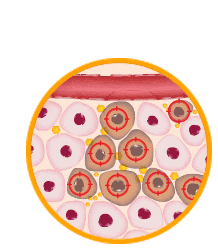

Step 5

DNA-based IL-12 is expressed in the local tumor microenvironment.

Step 6

Immune cells are educated to recognize the patient’s cancer.

Step 7

Immune cells are educated to recognize the patient’s cancer.

Step 8

Educated immune cells identify and attack tumors throughout the body.